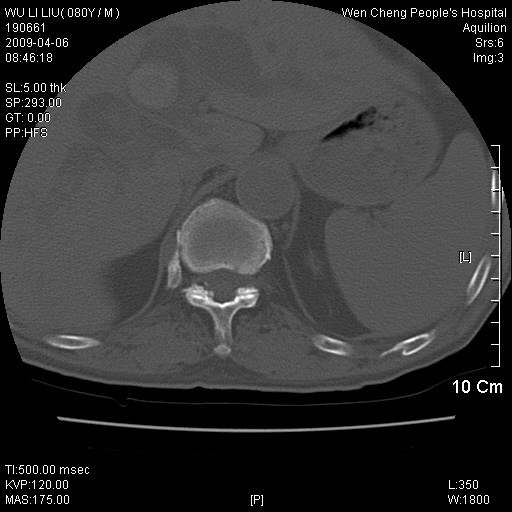

以下是引用zjzjr在2009-4-7 12:13:00的发言:[br]支持多发性转移瘤,右股骨颈骨折,腰椎亦有压缩性骨折.肝内胆管结石伴胆内外胆管扩张,左肾结石.

以下是引用liaoqiang在2009-4-7 8:44:00的发言:[br]考虑多发性骨髓瘤伴肝肺转移、肝内胆管结石、左肾结石、右股骨颈骨折。

以下是引用余辉在2009-4-7 8:52:00的发言:[br]椎骨及骨盆骨质疏松,骨破坏主要累及椎体,各骨破坏较广泛,各病灶边缘均较清晰锐利,血沉增快,白细胞增高.支持考虑多发骨髓瘤,建议查本尿周氏蛋白.[br]胆内胆管及左肾结石[br]右股骨颈骨折,考虑病理性